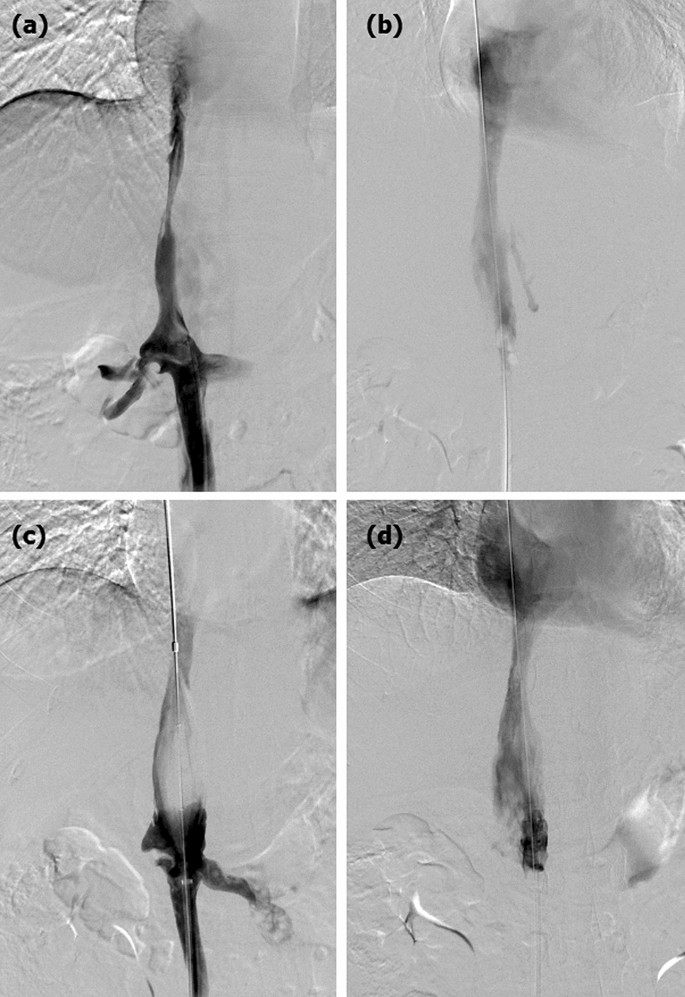

The median length of occlusive IVC was 18.5 mm before the procedure, which decreased significantly after the procedure (p < 0.0001). The mean diameter of the IVC lesion was 3.5 ± 2.5 mm before recanalization, which increased to 7.0 ± 2.0 mm after the procedure (p < 0.0001). The relative normal diameter of the proximal IVC did not change significantly within 6 months after the procedure. The diameter of distal IVC decreased significantly after the procedure, which indicated that dilation of the distal IVC had occurred before the procedure due to obstruction (Fig. 3). Blood flow of the distal IVC increased significantly during follow-up (p < 0.0001, Table 3).

Color Doppler ultrasonography. Segmental occlusion was shown in the proximal IVC (a, b). Partial patency was shown in the dilated IVC after angioplasty (c, d).